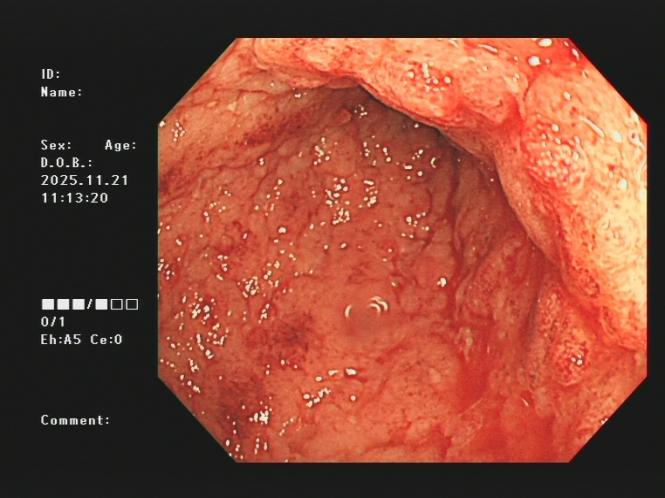

3.下消化道出血常见病因包括痔疮、肛裂、肠息肉、结肠癌、肠道憩室、炎症性病变(溃疡性结肠炎、缺血性肠炎、 感染性肠炎等)。以下是一些常见的下消化道出血内镜图片:

结肠癌、溃疡性结肠炎及缺血性肠病出血